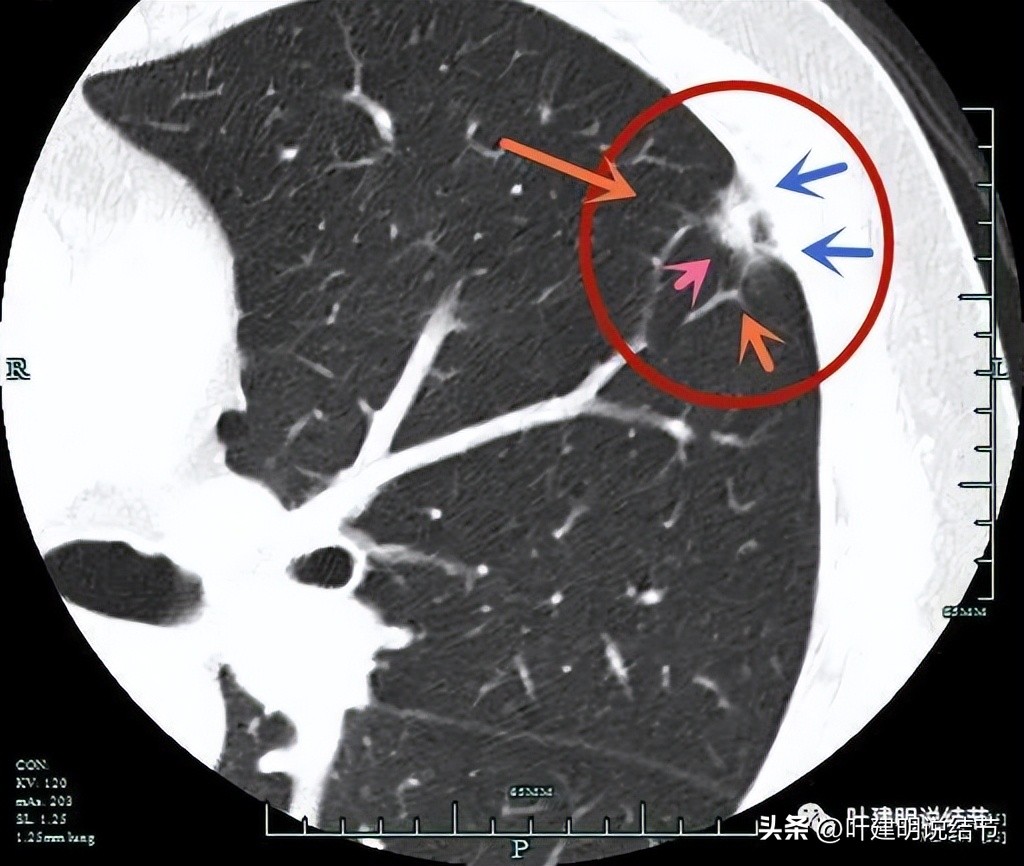

2022年11月时,结友来杭州市肿瘤医院,到我门诊就诊,我给申请做了平扫加靶扫描,结果影像如下:

病灶此次显示呈磨玻璃密度,轮廓较清,并有血管走向病灶(桔色箭头)。

病灶密度显高,像混合磨玻璃,并有明显血管走向病灶(桔色箭头),部分边缘有毛刺征(紫色箭头)。

病灶实性成分较多(粉色箭头),有分叶(砖色箭头)、有毛刺(紫色箭头)、有胸膜牵拉(蓝色箭头)。

上图层面明显是典型的恶性表现,收缩力强,蝴蝶征!分叶征、胸膜牵拉、实性成分、毛刺等均明显。

边缘区显散。

下面是靶扫描图像显示了更清楚的细节信息:

病灶密度不均,混合磨玻璃,有胸膜牵拉(蓝色箭头)、有血管多支走向病灶(桔色箭头),实性成分明显(粉色箭头)。

血管征明显,血管显得是异常增粗的,它没有越往远心端越细(桔色箭头);病灶边缘有毛刺征,整体轮廓较清,胸膜有牵拉的征象。

病灶边上有血管弯征(细桔色箭头),表面有浅分叶(砖色箭头),整体轮廓较清(红色箭头),而且显得密度不均杂乱。

密度不均,血管征,毛刺征。

上图粗桔色箭头示血管进入病灶后异常增粗、毛糙,成为偏实性成分。

灶内实性成分明显。

实性成分,微血管进入以及胸膜牵拉。

微血管进入,实性且杂乱的密度。

影像再判断:

看了2022年11月份的影像,这个已经是非常典型的恶性表现了,而且必为浸润性腺癌,不会是原位癌或微浸润性腺癌之类。主要的困惑是8个月前病灶并不像恶性,更符合慢性炎,这肿瘤进展得挺快。如果再过半年或一年复查,可能就更麻烦了。回头看,当时灶内其实只有微小的实性成分,而且周围区域的磨玻璃成分轮廓不清,瘤肺边界模糊,收缩力也弱。现在这样,必是该尽快手术了的。